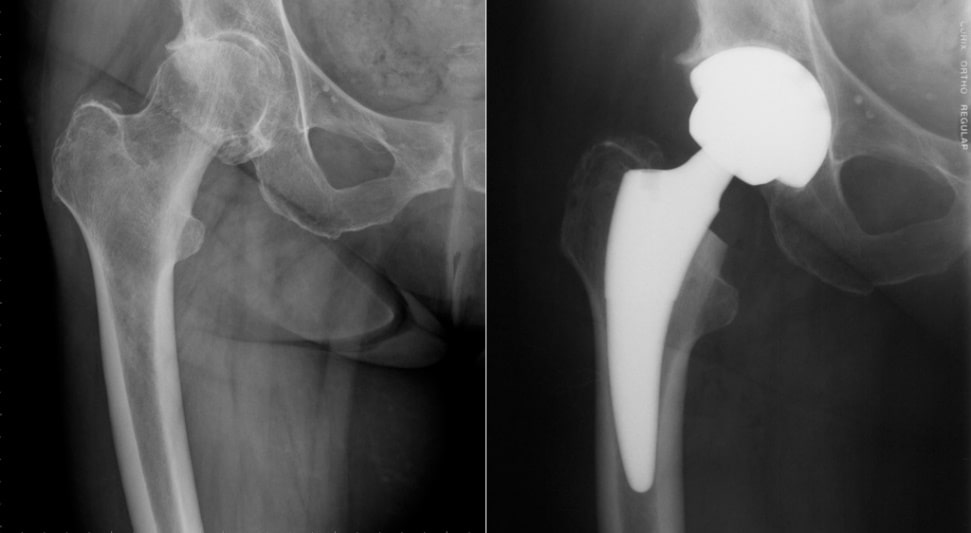

За последние 3 года в клинике совместно с кафедрами для оказания высокоэффективной многопрофильной медицинской помощи в соответствии с международными стандартами внедрены и  широко используются новые высокотехнологические виды диагностики и операций: дуплексное сканирование сосудов внутренних органов и конечностей; эхокардиография; артроскопия; эндопротезирование тазобедренного и коленного сустава; ангиопластика и стентирование   сосудов конечностей; стентирование коронарных артерий; стентирование холедоха; лапароскопические операции на органах брюшной полости (эхинококкэктомия, резекция печени, фундопликация, спленэктомия, холедохолитотомия, герниопластика, адреналэктомия); эмболизация маточных артерий при миоме, установка кавафильтра для профилактики тромбоэмболии легочной артерии; вмешательства при портальной гипертензии: эмболизация селезеночной артерии; факоэмульсификация с имлантацией интраокулярной линзы (ФЭК+ИОЛ), тоннельная экстракция катаракты с имплантацией интраокулярной линзы (ТЭК+ИОЛ); ультразвуковая денситометрия - предназначенная для оценки прочности костей, т.е. плотности, микроструктуры, эластичности, толщины кортикального слоя без лучевой нагрузки; поляризационная микроскопия – для выявления суставной жидкости при подагрических артритах; определение микроальбуминурии – для ранней диагностики диабетической нефропатии   и мн.др.

Тос суяги билан сон суяги эндопротези

(олдинги ва кенги холати)